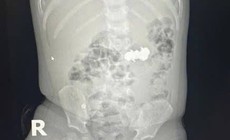

Cụ ông 90 tuổi nguy kịch sau bữa cơm tối

Camera bệnh viện - 06/10/2025 17:07SKĐS - Bệnh viện Bệnh Nhiệt đới Trung ương vừa cứu sống thành công cụ ông N.V.S (90 tuổi, ở Hà Nội) bị tắc nghẽn đường thở trong lúc ăn tối.